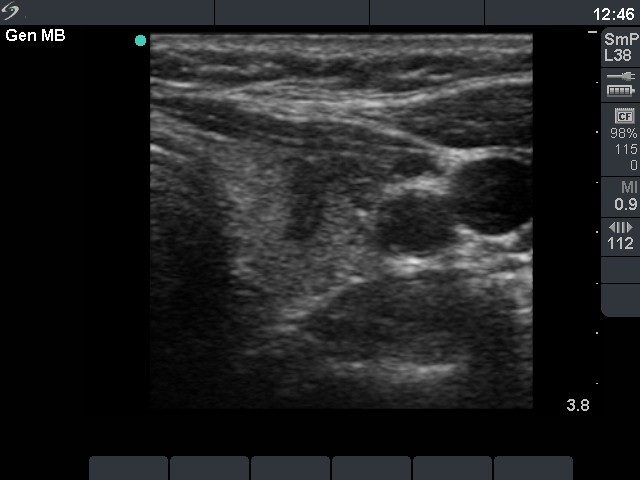

Left lobe, transverse scan. There is a hypoechogenic lesion having lobulated margins in the ventral part of the lobe.

Right lobe, longitudinal scan